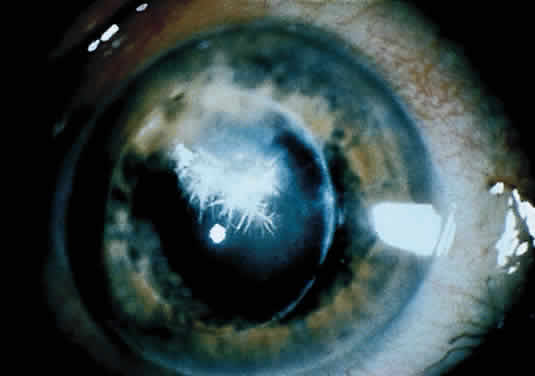

Infectious crystalline keratopathy is most commonly associated with S. viridans infection.43–45 This keratitis is characterized by discrete, white, crystalline, or fern-like stromal opacities, often under an intact epithelium, that are slowly progressive and have little associated corneal inflammation (Fig. 7). There is a strong association with prior topical corticosteroid therapy or penetrating keratoplasty. The condition has been termed infectious crystalline keratopathy and also has been reported with other organisms, including Haemophilus aphrophilus, Peptostreptococcus, and Staphylococcus epidermidis, as well as the fungal infections Alternaria and Candida tropicalis.46–49